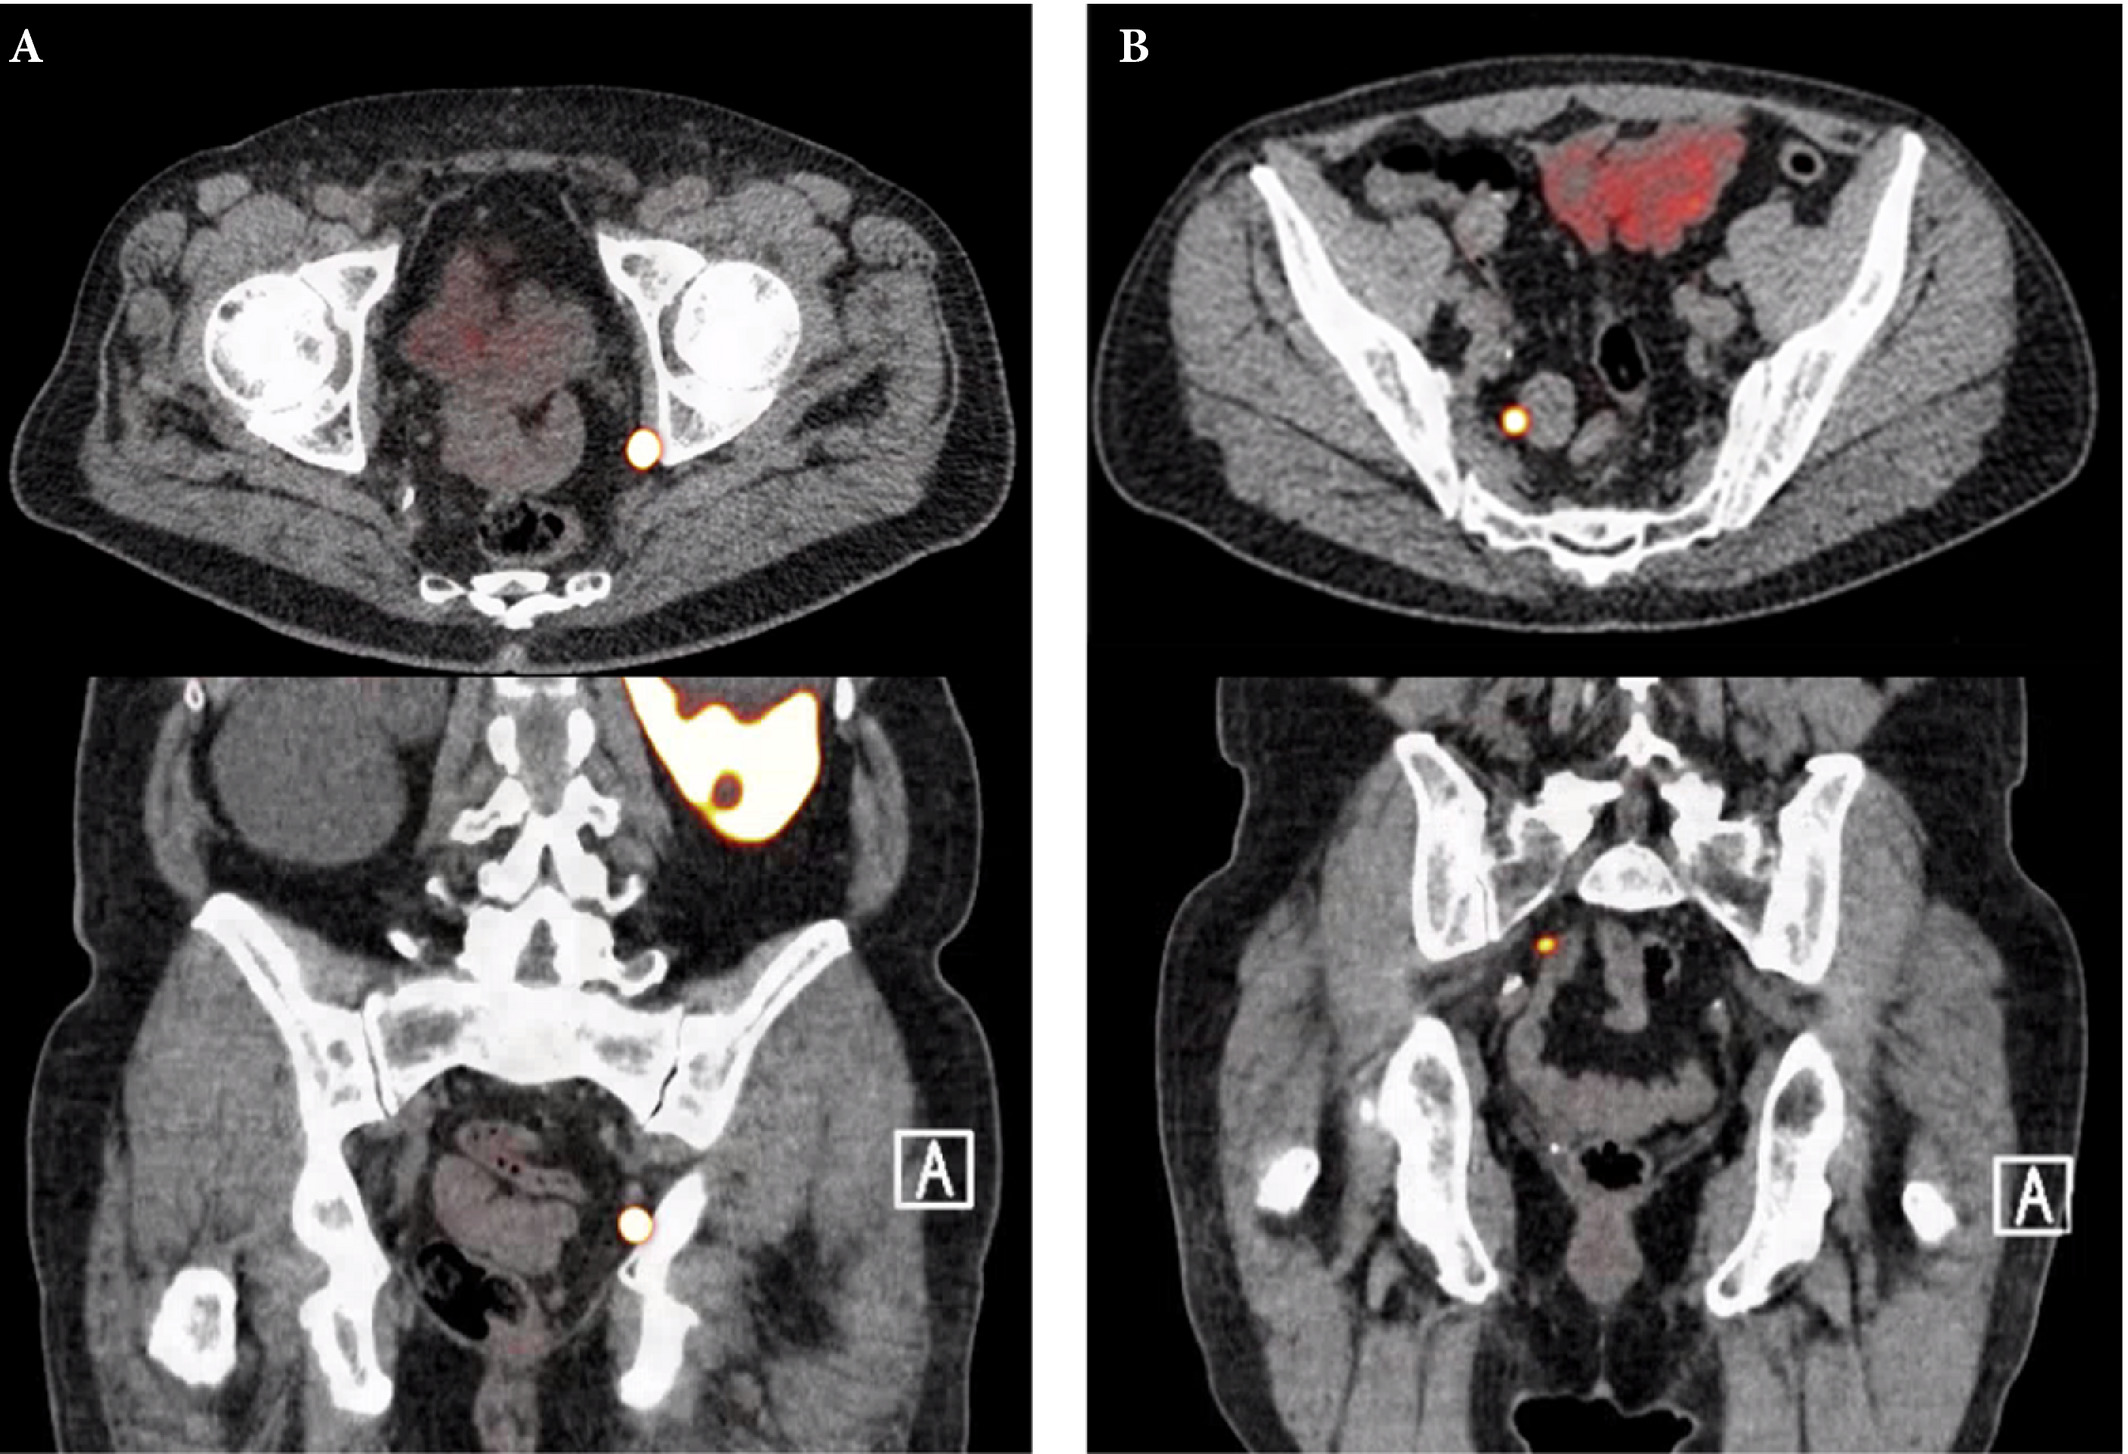

Fig. 1. Axial and sagittal plane gallium‐68 prostate‐specific membrane antigen positron‐emission tomography /CT images of two patients with locoregional lymph node recurrence after initial curative treatment. The metastasis in patient A is located in the obturator area and the metastasis in patient B is located in the presacral area.

Fig. 1. Axial and sagittal plane gallium‐68 prostate‐specific membrane antigen positron‐emission tomography /CT images of two patients with locoregional lymph node recurrence after initial curative treatment. The metastasis in patient A is located in the obturator area and the metastasis in patient B is located in the presacral area.